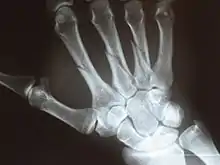

The five metacarpal bones, numbered. Left hand, anterior (palmar) view.

os primum metacarpale / os metacarpale I

os secundum metacarpale / os metacarpale II

os tertium metacarpale / os metacarpale III

os quartum metacarpale / os metacarpale IV

os quintum metacarpale / os metacarpale V